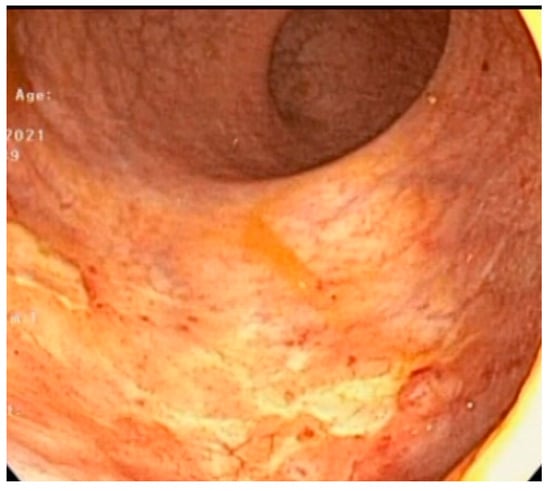

Diode Laser Therapy for Radiation-Induced Vascular Ectasia: Long-Term Results and Cost Analysis

3. Results